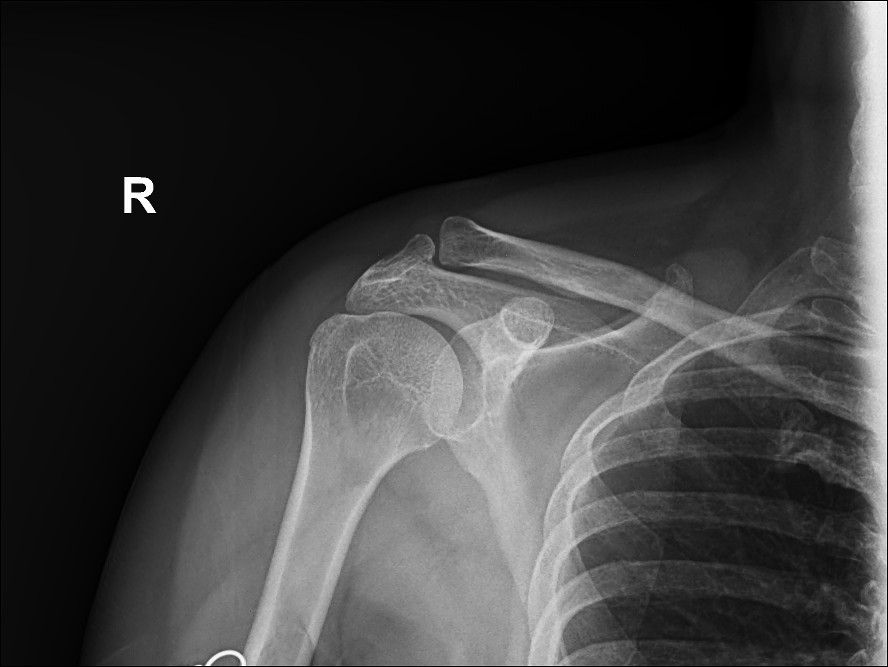

AP

shoulder X-ray to evaluate pain, injury, or discomfort in the shoulder joint. Common reasons include:

- Fractures: Identifying breaks in the humerus, scapula, or clavicle.

- Dislocations: Confirming if the humeral head is out of the glenoid cavity.

- Arthritis: Detecting degenerative changes in the joint.

- Bone abnormalities: Identifying bone spurs, infections, or tumors.

- Soft Tissue Calcification: Spotting calcific tendinitis

Internal rotation view

Radiographic projection used to visualize the shoulder joint, specifically highlighting the lesser tubercle of the humerus in profile medially